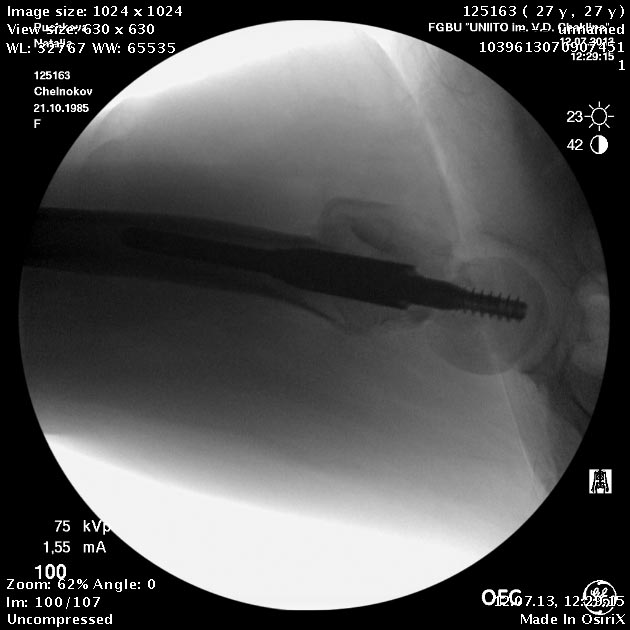

Пациентка приехала на этой неделе. Сегодня сделали правое бедро. Удалили

винты, сделали чрескожную вальгизирующую остеотомию, зафиксировали

Affixus. Второе бедро будем делать недели через 2.